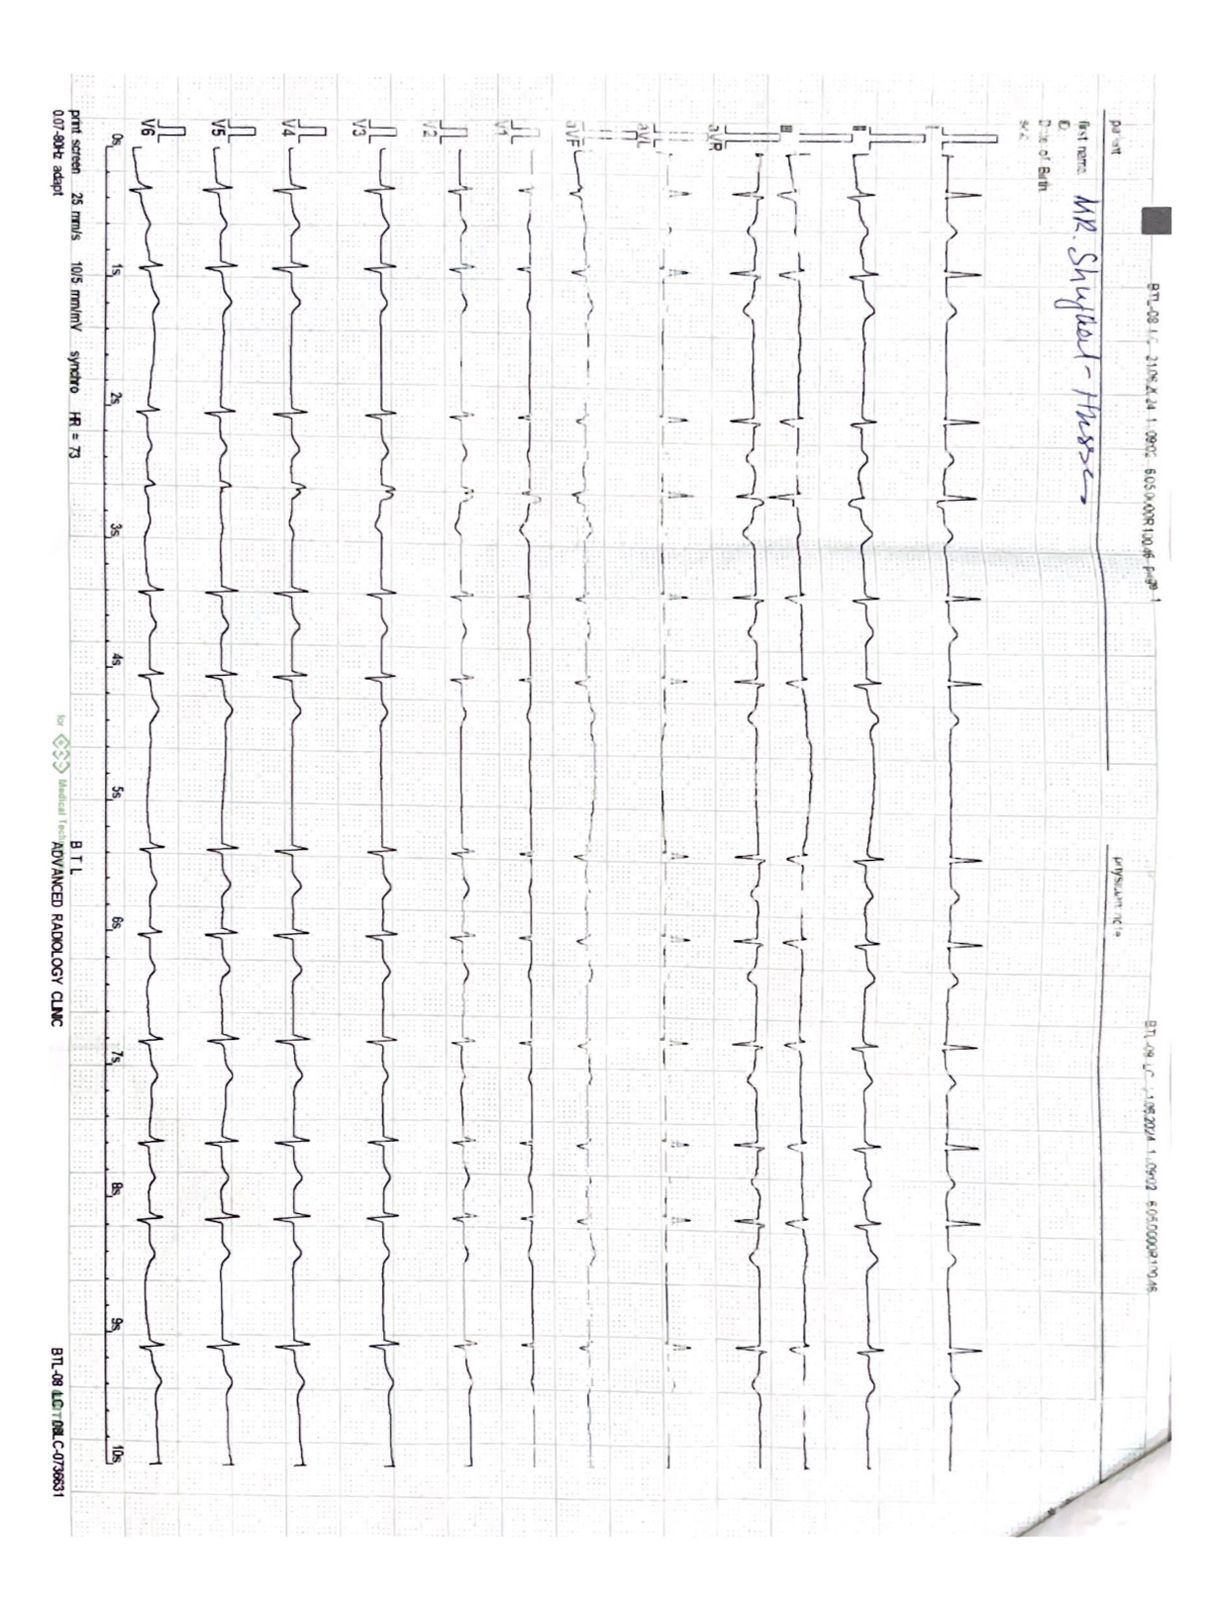

Hello Doctor, Hope you are fine. My father age 60 was facing some short breathing issue due to which we conducted complete blood and urine test which seems to be normal but in echo there are some changes showing can you please guide me with this and the treatment. Thank you

ecg showed significant changes

i would suggest u for complete cardiac work up of your father as soon as possible in good cardiac set up